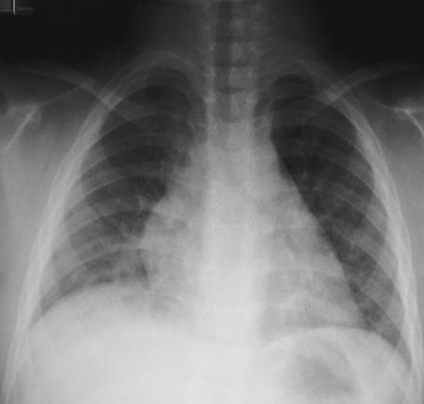

大叶性肺炎

(lobar pneumonia)

16岁患者患大叶性肺炎:

胸部 X 线检查所见:右下中

叶片状阴影,向基底部密度

增加